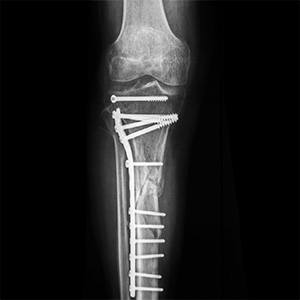

ORIF of the Knee Fracture

A knee fracture is a break in the continuity of bone within the knee. This can involve the tibia (shinbone), kneecap (patella), or femur (thigh bone).